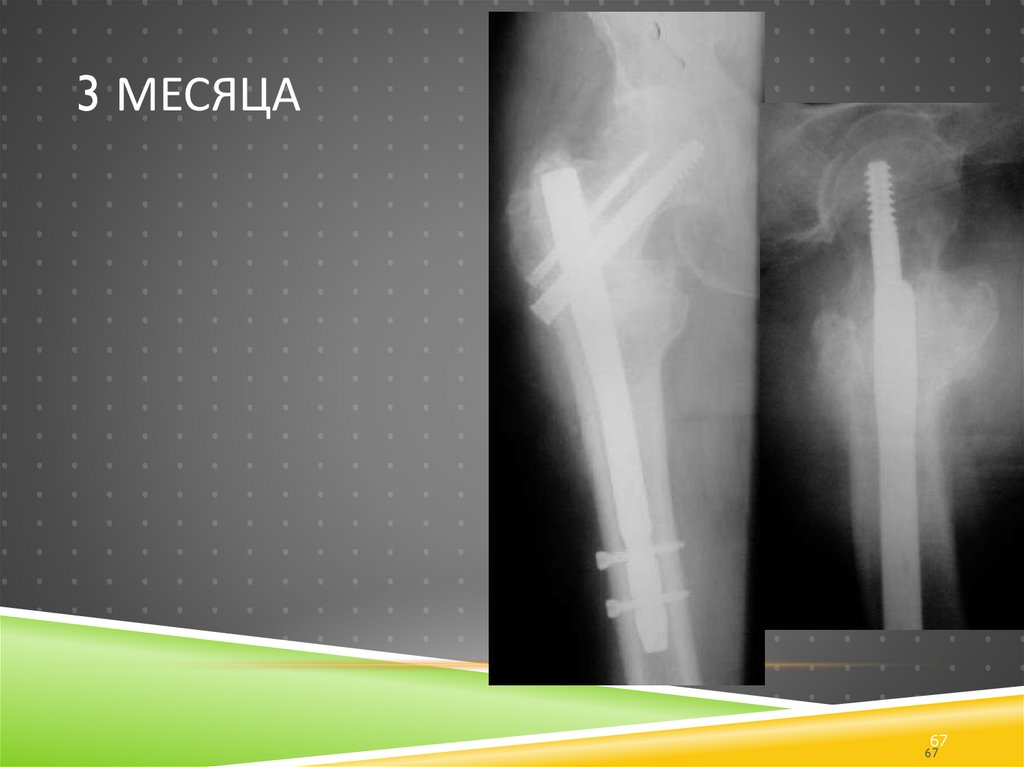

3 месяца

67. 3 месяца